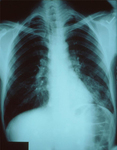

Chlamydia pneumoniae infection

AP CXR showing pneumonia of the left lower lobe with early consolidation, the aetiology of which was unknown.

CDC/ Dr Thomas Hooten; used with permission